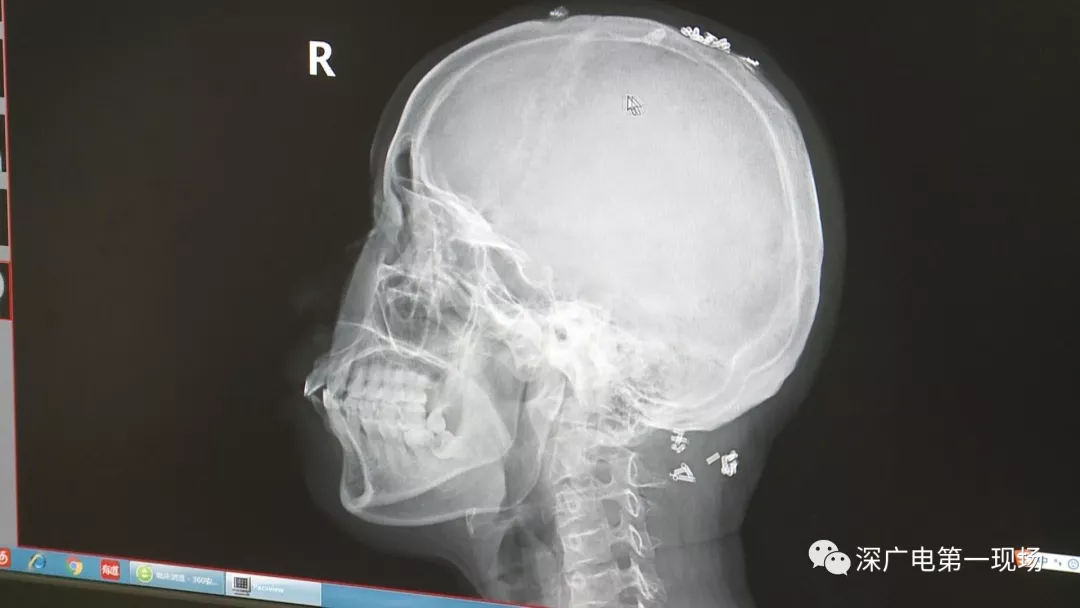

從X光影像圖片中可以看到

患者周身布滿了彈簧圈

深圳大學(xué)總醫(yī)院神經(jīng)外科副主任醫(yī)師陳富勇介紹,當(dāng)時(shí)檢查的時(shí)候發(fā)現(xiàn),該患者從頭部到腿部,基本上每個(gè)地方都有彈簧,很難數(shù)清具體數(shù)目。

陶主任表示,將這些彈簧圈取出也是一項(xiàng)大的工程,因?yàn)橛械亩家呀?jīng)形成了包塊,所以想要取出還得先定位,再挨個(gè)手術(shù)取出,目前醫(yī)院方面已經(jīng)將患者頭部和頸部的部分取出。